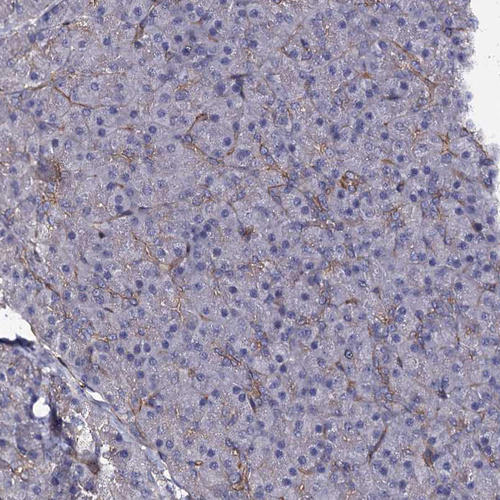

Immunohistochemical staining of human small intestine shows strong membranous positivity in glandular cells.